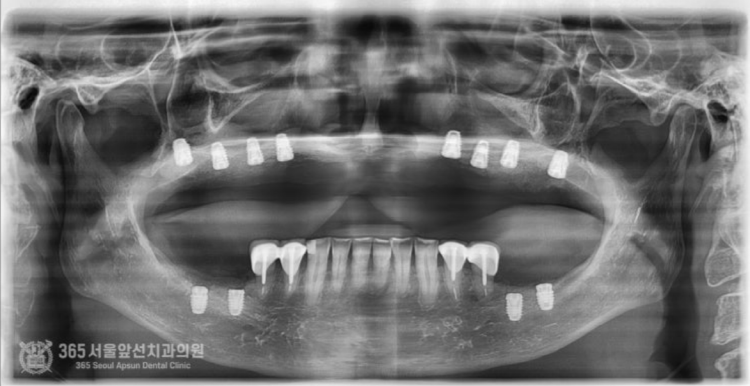

촬영일시: 2024.06.07. 처음 오셨을때 엑스레이 사진입니다. 윗턱과 아래턱 모두 뼈가 매우 적은편입니다. 특히 윗턱의 앞니쪽은 뼈가 고작 3mm밖에 존재하지 않았습니다. 매우 난증례에 해당한다고 볼 수 있겠습니다. 앞니 부위 뼈가 매우 부족하고(3mm) 어금니쪽도 전체적으로 뼈가 매우 적었습니다. 앞니와 어금니의 부족한 뼈를 만들어내면서 임플란트 식립을 계획했습니다. 통상적으로 윗턱에서 뼈가 부족할때 사용하는 수술방법으로 상악동거상술이라는 잘 알려진 술식이있는데요. 상기 환자분의 경우, 앞니쪽까지도 뼈가 부족했기에 코로 접근해서 부족한 뼈를 만들어 내는 비강거상술까지 동반하여 임플란트 수술을 진행했습니다. 촬영일시: 2024.08.10. 좌우측 상악동 거상과 비강거상을 동반하여 윗턱에 임플란트 8개를 식립했습니다. 지금까지 만나뵈었던 많은 환자분들 중 뼈의 상태가 매우 안좋은 편에 속하셨으며 매우 난해한 증례였습니다. 그렇지만 수술은 성공적으로 잘 마무리되었습니다. 위아래 전체 임플란트를 식립한 후 엑스레이 사진입니다. 임플란트가 가지런히 잘 배열되어있습니다 ㅎㅎ 지르코니아라는 재료를 사용하여 치아색상으로 단단하게 보철물도 제작했습니다. 촬영일시: 2024.12.29. 최종적으로 마무리된 엑스레이 사진입니다. 촬영일시: 2024.12.29. -노란색: 원래 환자분의 윗턱뼈 -주황색: 상악동거상술을 통해 만들어진 뼈 -보라색: 비강거상술을 통해 만들어진 뼈 최종적으로 치료가 완료된 후 구강내 사진입니다.